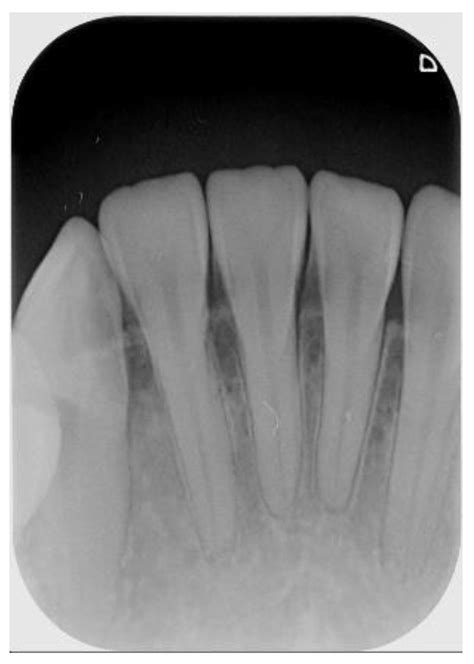

When you visit your dentist for a toothache or a routine check-up, they may recommend a specific type of dental imaging to get a clearer picture of your oral health. Among the various diagnostic tools available in modern dentistry, the Periapical X Ray stands out as an essential imaging technique. Unlike broader panoramic X-rays that capture the entire jaw, a periapical image focuses on one or two specific teeth, providing an incredibly detailed view of the tooth from the crown down to the very tip of the root and the surrounding bone structure. Understanding what this procedure entails can help alleviate any anxiety you might feel about your upcoming dental appointment.

A Periapical X Ray, often referred to simply as a "PA," is a close-up, high-resolution diagnostic image. The term "periapical" literally translates to "around the apex," with the apex being the tip of the tooth root. This specific type of X-ray is designed to show the entirety of the tooth—from the biting surface (crown) down to the root end—as well as the surrounding supporting bone.

• Detecting Abscesses: To see infections or pockets of pus forming at the tip of the root.

• Identifying Bone Loss: To evaluate the health of the bone supporting the teeth, which is crucial for diagnosing periodontal disease.

• Trauma Assessment: To check for fractures or damage to the root after an injury to the mouth or jaw.